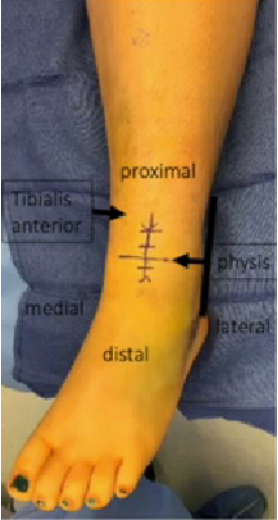

图源:DOI: 10.1302/2058-5241.6.200042.